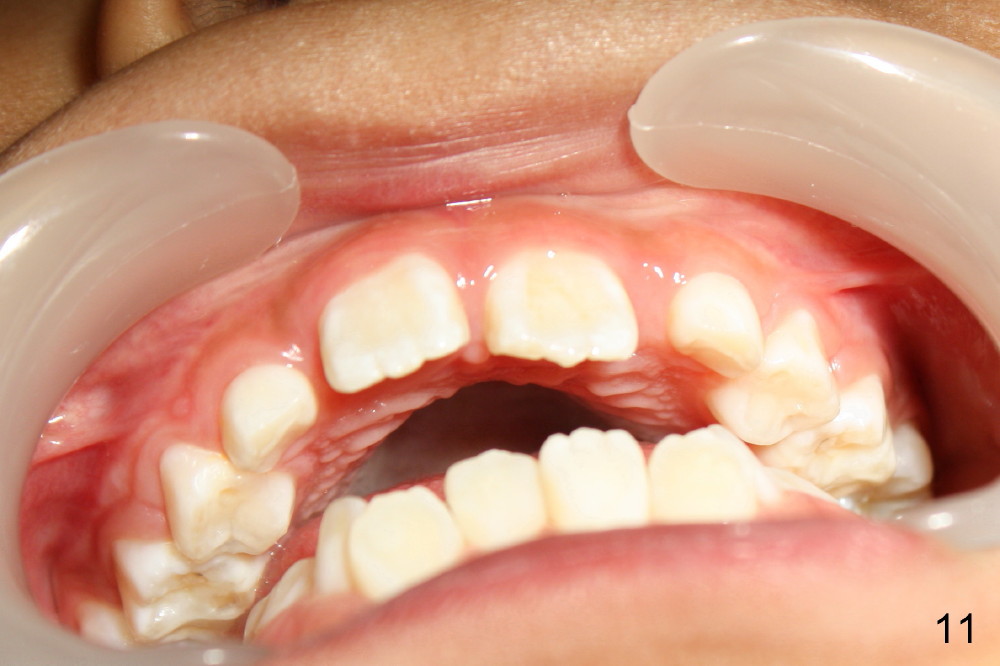

Now Devon is 7.5 years old. There is diastema between the centrals (Fig.9). #9 is in cross bite (Fig.10,11), while the lower incisors are crowded.

现在Devon七岁半,中切牙之间缝隙大(图九至十一:8,9),乳侧切牙已经脱落,但是没有足够间隙让恒侧切牙(图九:7, 10(C, H:乳尖牙))萌出,左上中切牙反合(图十:9),下切牙拥挤。